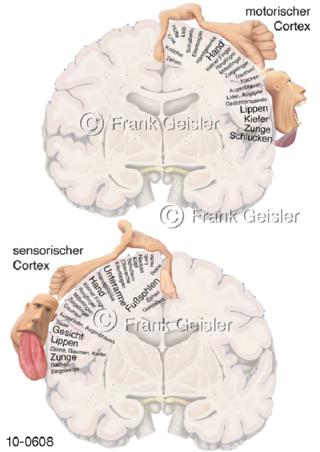

Bildergalerie Nervensystem

Bilder zum Nervensystem,dem Gehirn, Teil des zentralen Nervensystem, Zentralnervensystem ZNSmit Rückenmark, Abbildungen zum Nervengeflecht (Nervenplexus), die Verflechtungen von Nervenfasern, aus der Wirbelsäule hervortretende Nervenäst sowie Nervenzellen der Nerven